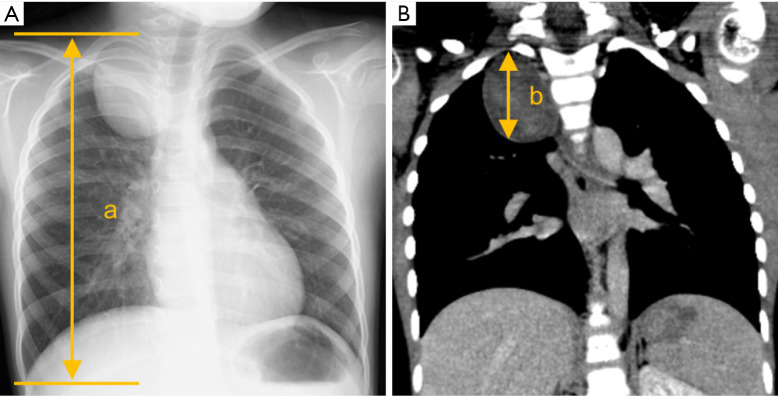

Data were collected from the medical records of Hokkaido University Hospital. Thoracic height was calculated using chest radiography because it was difficult to measure the maximum diameter of the thoracic height using the coronal section of a chest computed tomography (CT), defined as the diameter from the apex of the lung to the bottom of the costophrenic angle (Figure 3A). The tumor height was calculated using the coronal section of the chest CT (Figure 3B) because the tumor height was difficult to measure using chest radiography in some cases due to the ambiguous margin of the lesion. The TTH ratio was calculated as tumor height divided by thoracic height (TTH ratio = b/a × 100%) (Figure 3). TV was calculated using the three dimensions from cross-sectional CT imaging (TV = length × width × height × π/6 mL), as previously reported (17). Postoperative complications were assessed using the Clavien-Dindo classification (19). Furthermore, the mediastinal compartments were divided into prevascular (anterior), visceral (middle), and paravertebral (posterior) compartments, which were defined by the International Thymic Malignancy Interest Group (20).

Figure 3.

Method for calculating the tumor-to-thoracic height ratio. (A) The thoracic height, defined as the diameter from the apex of the lung to the bottom of the costophrenic angle, was calculated using chest radiography. (B) The tumor height was calculated using the coronal section of a chest computed tomography image. The TTH ratio was calculated using the following formula: TTH ratio = b/a × 100%. a is defined as thoracic height and b is defined as tumor height. TTH, tumor-to-thoracic height.